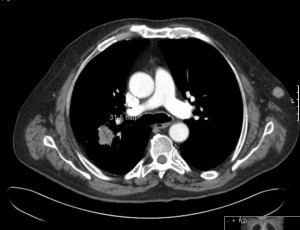

Confirmamos que se trata de un nódulo pulmonar para hiliar de 3cm en el segmento posterior del lóbulo superior derecho, homogéneo y de contornos lobulados.